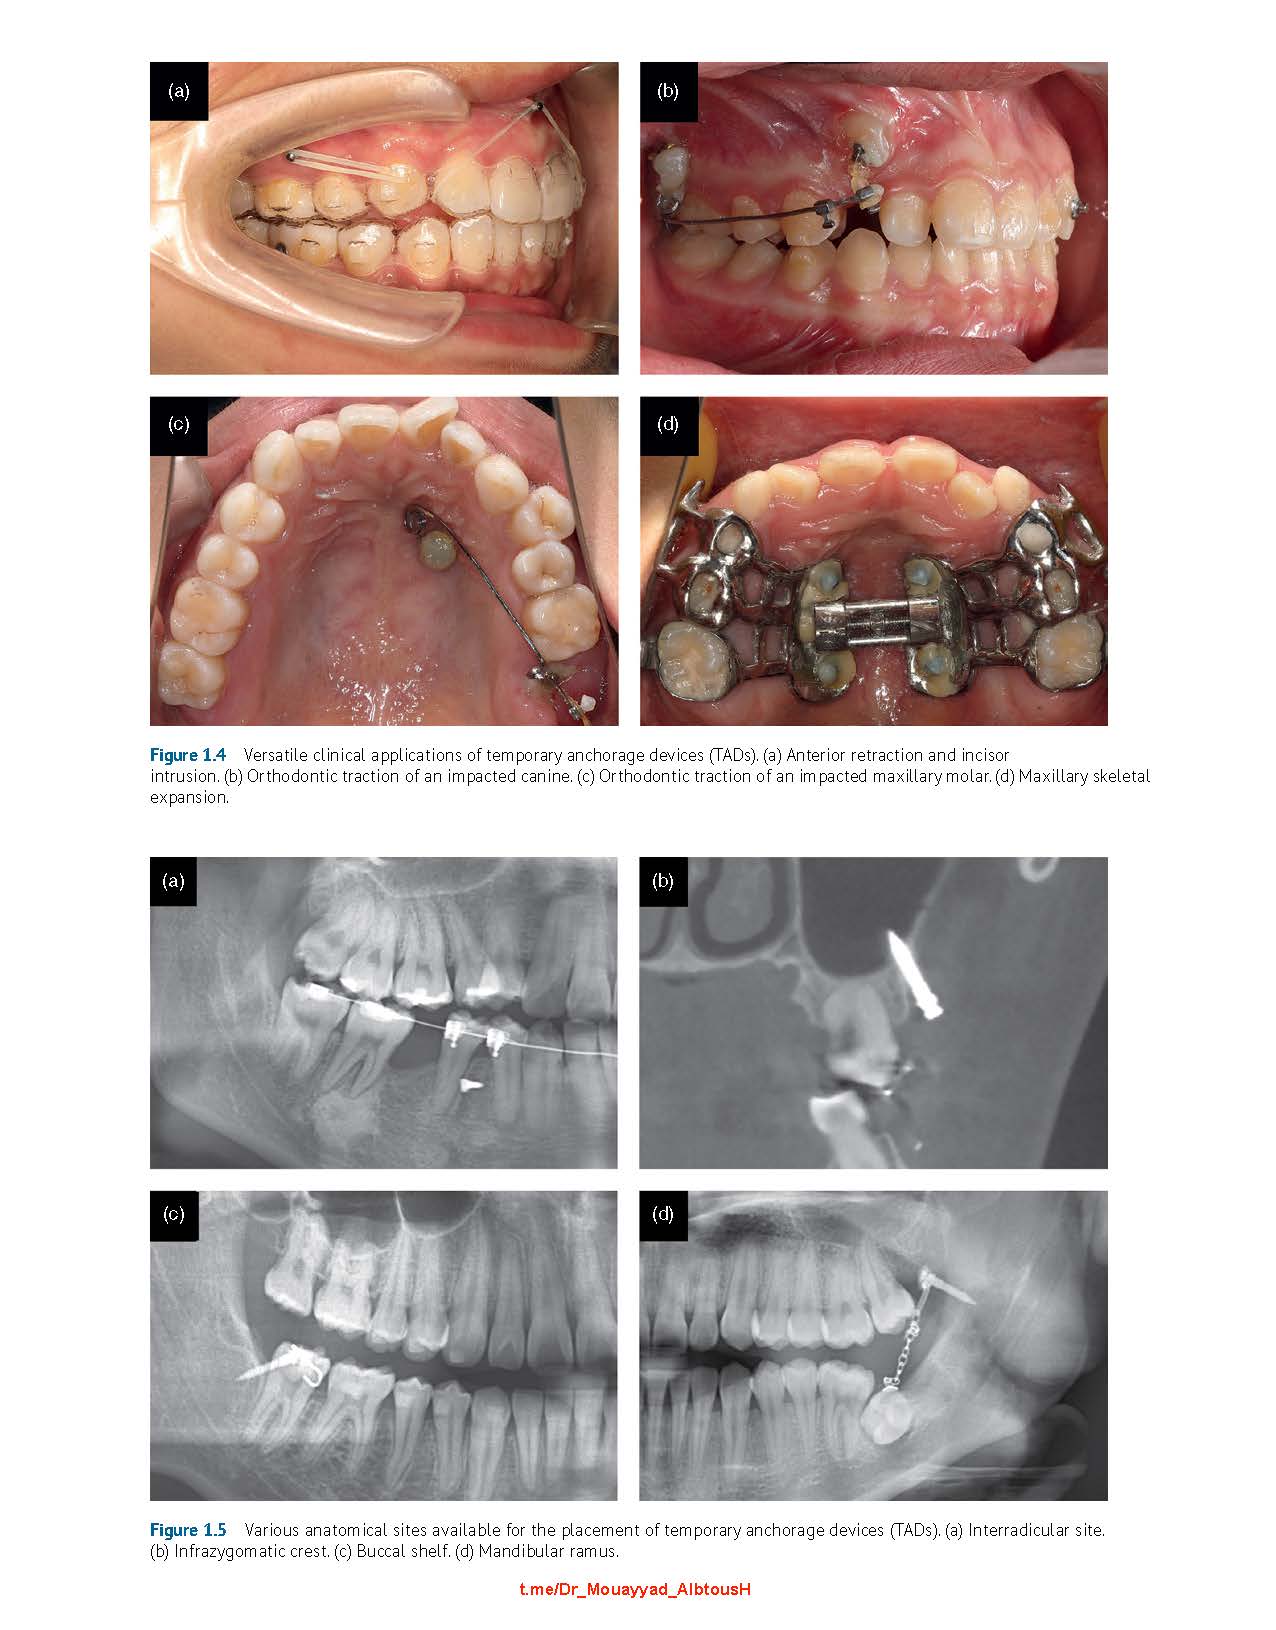

Although numerous case reports demonstrate the versatility of TADs (e.g., incisor intrusion, molar distalization or protraction, molar intrusion, skeletal expansion, and maxillary protraction), many clinicians struggle with:

• Identifying the optimal mini-implant insertion sites for specific tooth movements

• Lacking confidence in placing mini-implants in anatomically challenging areas, even when they understand the theory